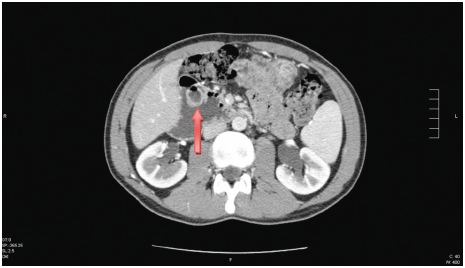

Institui-se antibioterapia com levofloxacina com apirexia ao fim de 4 dias e tem alta para a consulta de Medicina Interna, onde realiza tomografia computorizada (TC) toracoabdomino- pélvica (fig. 1) que demonstra, ao nível da 2ª porção do arco duodenal (DII), a partir da vertente externa da parede, imagem que parece corresponder a invaginação parcial, cujo conteúdo é semelhante ao do arco duodenal adjacente, não se identificando lesões sólidas à periferia deste segmento de intestino delgado que possam constituir ponto de partida para a invaginação. O duodeno encontrasse distendido (5,5 cm) a jusante deste nível e até à zona dos vasos mesentéricos (3.a porção), não se identificando qualquer causa obstrutiva subjacente.

Figura 1 TC com contraste revelando imagem de aspeto sacular com sinal «halo» e dilatação do duodeno (5,5 cm) em DII. A seta indica o DDI.